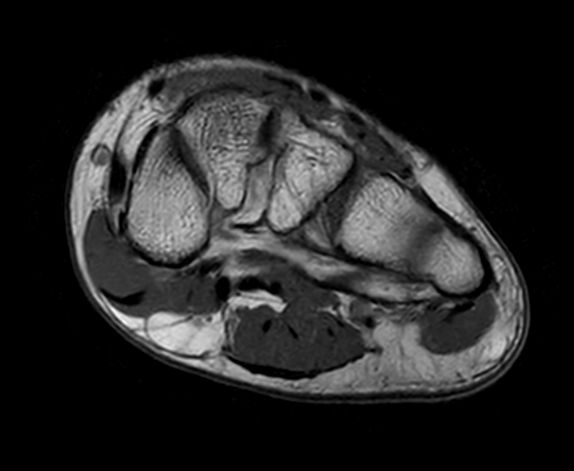

SmartSpeed Forefoot imaging

Suzukake Central Hospital, Japan

This forefoot ExamCard includes 3 orientations and several different contrasts. SmartSpeed is used to increase imaging speed while delivering outstanding image quality.

Axial T2w TSE

-

Axial T1w TSE

Axial STIR TSE